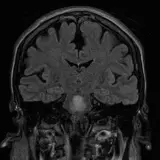

Over 2,100 interactive radiology cases, curated by radiologists for your level of training. Scroll, window, and view cases full screen — just like on PACS. Click linked findings in each writeup to jump straight to them on the image. Cases include sample reports, a focused discussion section, original illustrations, and videos.

Neuro Fellowship — a course tailored for fellows and practicing radiologists with in-depth reviews of advanced neuro topics like brain tumors, featuring rare diagnoses, differentials, and clinical pearls.

完全交互式病例,配备您在 PACS 上期待的各项工具——滚动、调窗、缩放、平移、测量、ROI 和全屏模式。

丰富的标注直接在病例图像上突出关键发现。点击病例讲解中的关联发现,即可跳转至其在扫描上的精确位置。

交互式病例

像在工作站 PAC 上一样滚动、平移、调窗和缩放

通过标注的影像发现与示意图高效学习